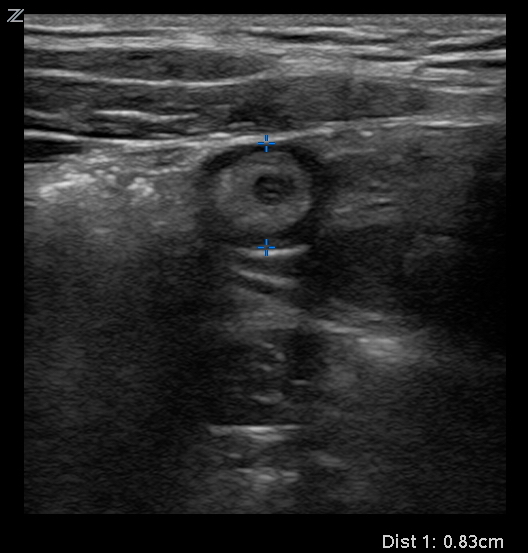

24yo F G2P1011 with hx of kidney stones presents complaining of right sided abdominal pain. The goals for this case are to recognize potential causes of right sided abdominal pain and the utility of using bedside US to narrow your differential and ultimately obtain your diagnosis.

appy measurement.jpg